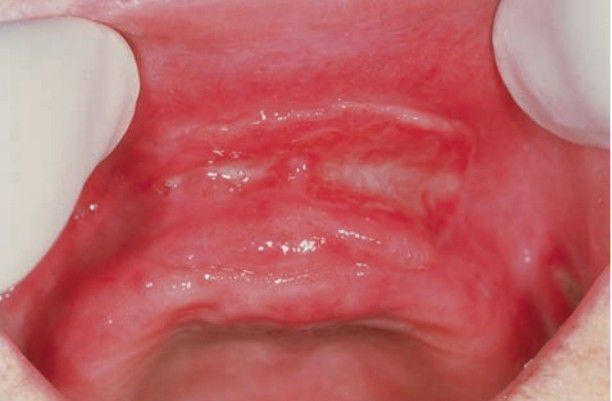

Denture-induced fibrous hyperplasia of oral mucosa is related to the chronic trauma produced by an ill-fitting denture. The process is essentially the same as the one that leads to traumatic fibroma, except that a denture is specifically identified as the causative age.